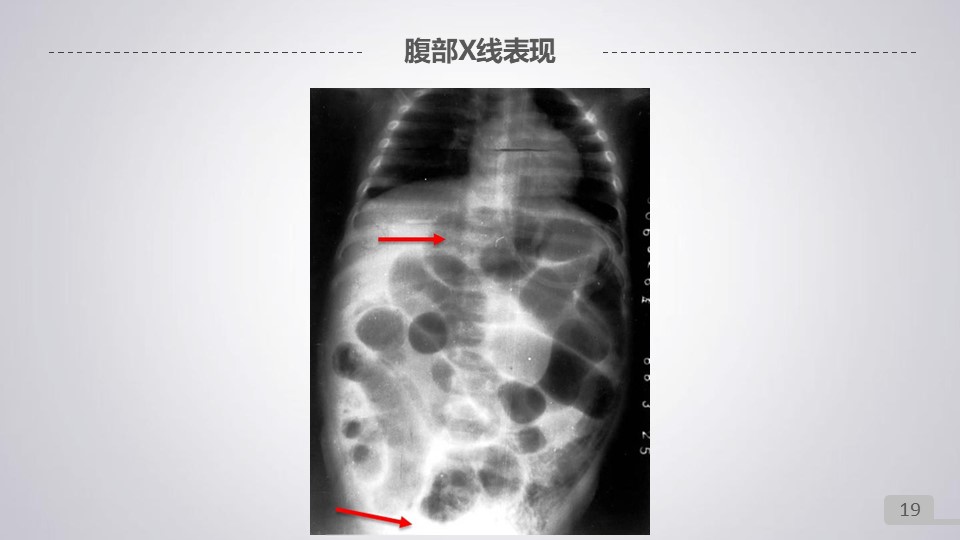

“新生儿坏死性小肠结肠炎PPT” 的相关文章